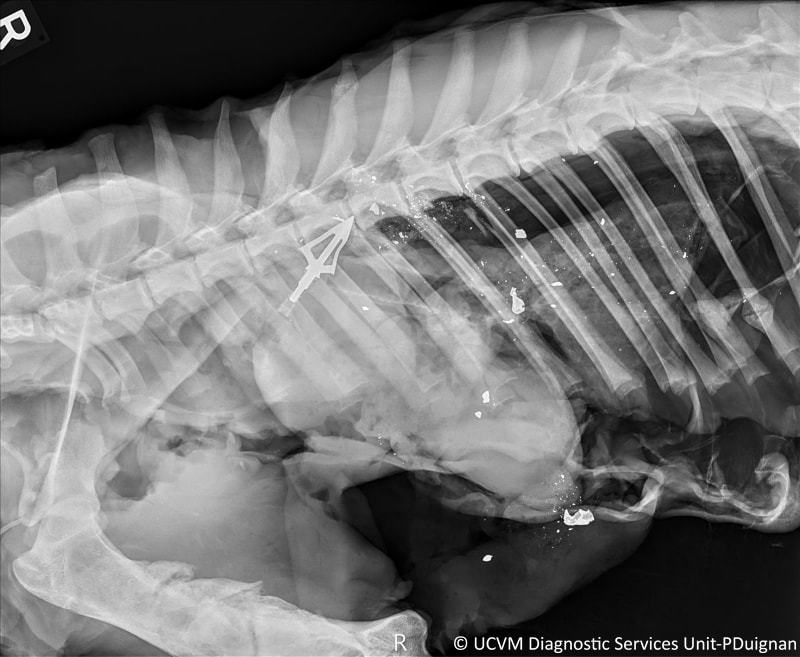

Species: Wild Mammal, Cougar

Specimen: Radiograph

Shown: Penetrating wound from arrow